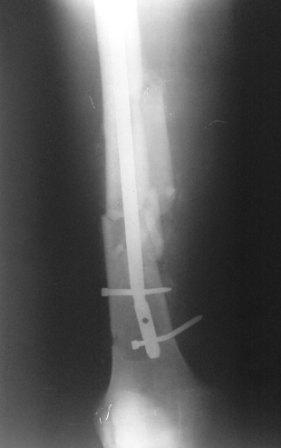

Пациент с политравмой. Выполнен помимо всего остеосинтез бедра стержнем. Поступил через месяц после операции с переломом фиксатора.У нас возникли разногласия по дальнейшей такике.Помогите пожалуйста советом! Пациент, 30 лет, после мотоциклетной аварии получил следующие повреждения: перелом бедра, перелом вертлужной впадины на противоположной стороне, перелом обоих предплечий, ЧМТ.Выполнен остеосинтез таза пластиной и остеосинтез бедра стержнем ChM. Во время операции стержень оптимальной длины оказался слишком "толстым" (420/11 мм) и пришлось выбрать более короткий гвоздь (400/10 мм). Через месяц возникла следующая картина: изгиб винтов и стержня, появилось смещение, имеется тугая подвижность в месте перелома.Предложено несколько выходов:- поменять фиксацию на более длинный гвоздь,- использовать ретроградную версию бедренного гвоздя,- поменять на накостный фиксатор (длинную LCP DF).В данном случае приобретать импланты придется за счет средств пациента, поэтому хотелось бы все тщательно взвесить.Уважаемые коллеги, помогите пожалуйста советом, как бы вы поступили в такой ситуации.

Да, такая картина заставляет план подкорректировать. После удаления стержня надо дистрактором одномоментно или, если не получится, постепенно восстановить длину. И для окончательного устранения антекурвации надо взять гвоздь потолще и подлиннее.

Уважаемый коллега. Боковая проекция еще раз свидетельствует о том, что в плане стабильности и биомеханики оптимальным будет ретроградный синтез с предварительным наложением дистрактора или применения ортопедической приставки, при этом нет необходимости вскрывать зону перелома, мне кажется имеюшийся угол искривления атакующего конца стержня позволит без технических трудностей её удалить. При отсуствии гибких риммеров антеградный реостеосинтез будет проблематичным, в плане блокировки теперь уж статическая фиксация оптимальна.